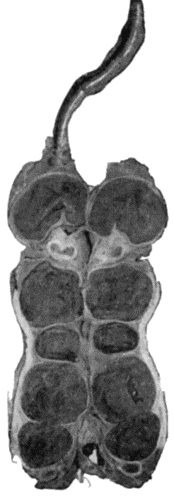

467 133.Skeleton of Rickety Dwarf

470 134.Changes in the Skull resulting from Ostitis Deformans

474 135.Cadaver, illustrating the alterations in the Lower Limbs resulting from Ostitis Deformans

475 136.Osteomyelitis Fibrosa affecting Femora